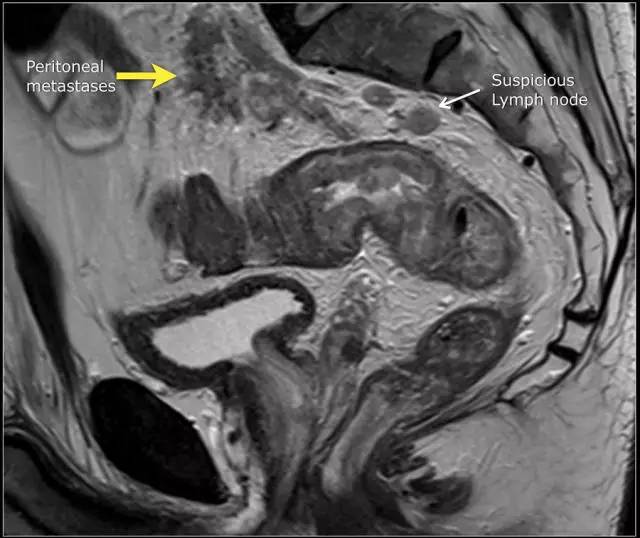

图 15 同一患者腹膜转移的矢状图(箭头),在直肠内还有可疑的淋巴结

T4b 分期,侵入周围器官

T4 期肿瘤侵犯周围结构,如盆壁、阴道、前列腺、膀胱或精囊,这类局部晚期患者需要进行长程放化疗和广泛切除。